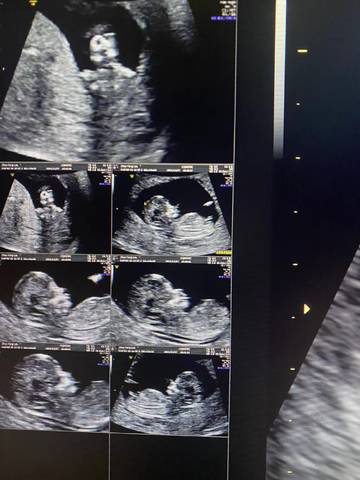

帮我看看是弟弟还是妹妹呀,我太好奇了,弟弟妹妹都是宝,好奇的睡不着????????

journal_insert_pic_1675836257journal_insert_pic_1675836258journal_insert_pic_1675836259

看起来像弟弟哦

男孩